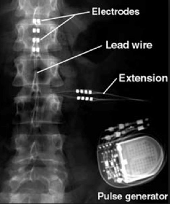

₦48,000.00Spines and Disc Care Pack – Spinal Cord Problems